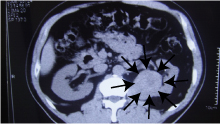

64歳、女性、上腹部痛にて来院、エコーにて膵臓部に腫瘍を見つけ、CTにても確認、外科手術が

施行された症例です

腹部CT検査

例)61歳の男性で腹部超音波にて偶然見つかった腎がんの症例です。

腹部CTでも確認されました。当然症状はありませんでした。外科手術が施行されました。

CT